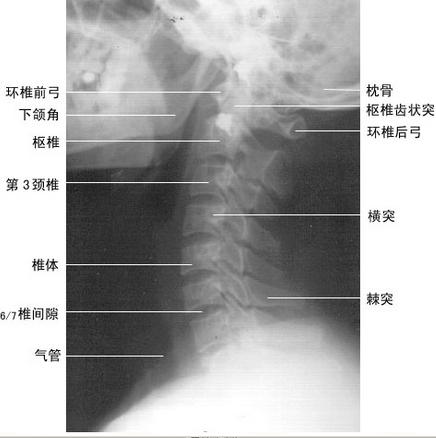

X线平片  包括胸部X线片和颈椎X线片。

颈椎结核起病时X线表现多不明显,一般在发病数月至1年才有阳性发现。中心型病灶早期表现为在一个或可在两个邻近的椎体中央骨松质中出现破坏透亮区,边缘模糊,周围一般无明显骨质增生现象。随着病变的发展,可见破坏区逐渐扩大,可以均等地向上、下两方扩展,或者以向一方破坏为显著如破坏严重,可使椎体产生相应的塌陷变扁。当结核病灶侵及其附近的椎间盘时使椎间隙变狭,如穿过椎间盘而侵及邻近的椎体时可见累及的一面骨质破坏。边缘型病灶早期表现为椎体前缘、上缘或下缘出现骨质破坏,常伴有附近的椎间隙狭窄。

这种病变多见于成人,病变一般发展较慢,有局限于两个椎体的倾向,中间的椎间隙可有明显的狭窄,两面的椎体有不同程度的破坏,有时可呈局限的缺损,类似许氏结节的表现。如果一个椎体的一面破坏严重,则其邻近的无明显破坏的椎体可以嵌入破坏区。

骨膜下型病灶较为典型的表现为一、二个椎体旁有明显的脓肿形成,但椎体无显著的破坏,仅周围与脓肿相邻部位边缘不清或不甚规则,椎间盘保持正常。其后在椎体前缘出现骨质侵蚀而凹陷,往往须用体层摄影才能清楚显示。局限于椎弓、棘突和横突的结核病灶甚为少见,表现为受累部位的骨质破坏,在其附近出现软组织肿胀阴影。寰枢关节结核则须摄开口位颈椎片。早期仅显示寰枢关节脱位或半脱位,而无骨质破坏。后期可见侧块、齿状突被破坏,甚至见到齿状突骨折。

椎前软组织阴影可增宽,气管被推向前方或偏于一侧,当脓肿穿破可见含气积液腔。晚期脓肿可见钙化影。